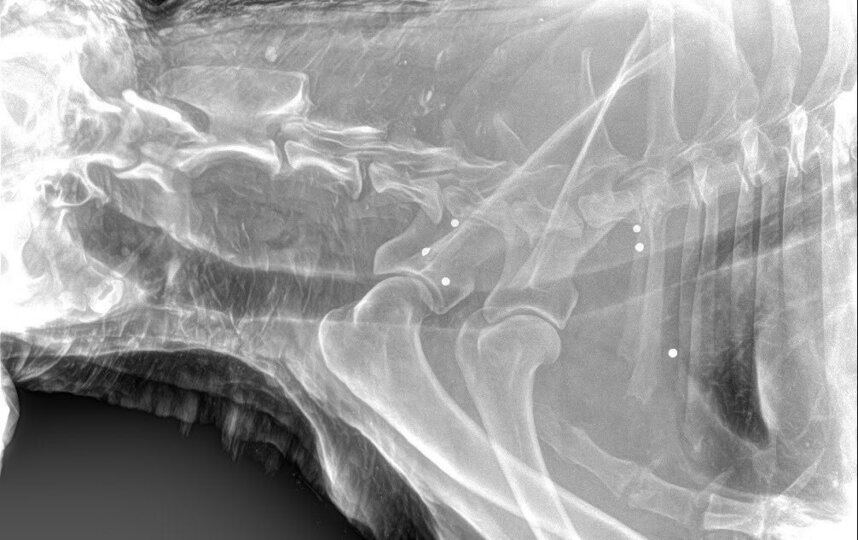

Под Петербургом выхаживают пса с огнестрельными ранениями

Специалисты привезли животное в ветеринарную клинику, где на рентгене стали видны многочисленные огнестрельные ранения. Из тела пса достали пули разной степени давности, сообщает телеграм-канал Mash на Мойке.